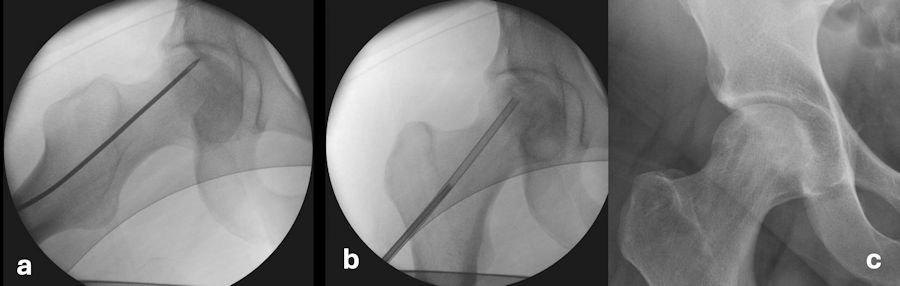

Femur başının yuvarlaklığının bozulmadığı ve çökmenin olmadığı evrelerde kalça eklemi koruyucu cerrahilerin başarısı %80’lerin üzerindedir. Bunun için kor dekompresyon ve greftleme adı verilen bir teknik tercih edilir. Önce ölü kemik bölgesine ulaşacak şekilde tüneller açılarak başın içindeki artmış basınç azaltılır. Bu tüneller aynı zamanda vücudun tamir hücrelerinin bölgeye ulaşması için yollar hazırlar. Geçmiş yıllarda 10-12 mm çapında büyük tüneller açılarak yapılan bu işlem, günümüzde çökme riskini azaltmak için küçük çaplı daha çok sayıda tüneller ile uygulanmaya başlamıştır. Bu işlem ameliyathane şartlarında, skopi (röntgen) kontrolü altında hasarlı bölgeye ulaşıldığından emin olunacak şekilde yapılır. Ölü kemik alanına 4-5 mm çapında çoklu tüneller açılır, bu tüneller içinden hasarlı bölgeye leğen kemiğinden alınan canlı kemik silindirleri yerleştirilir ve iyileşmeyi uyarmak için kök hücreden zengin kemik iliği konsantresi ve PRP karışımı eklenir. Böylece hem kemik içi artmış basınç normale getirilir hem hasarlı bölgeye canlı kemik ile mekanik destek sağlanır hem de kök hücreler ve PRP’nin içerdiği büyüme ve iyileşme faktörleri bölgeye ulaştırılmış olur. Ameliyat sonrası 6 hafta süreyle koltuk değneği ile kısmi yük verilerek yürümeye izin verilir. Altı ay süreyle koşma ve zorlayıcı sporlar uygun değildir. Bu süre içinde HBO ve bisfosfonat tedavisi devam eder.